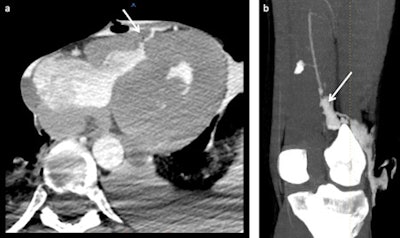

The development of postmortem CT angiography (PMCTA) represents a significant step forward to minimally invasive autopsies, but considerable work still has to be done before it can replace the conventional autopsy, Swiss researchers have found.

The research group in Lausanne is doing multiple studies involving the technique of multiphase PMCTA (MPMCTA). Also, different research projects of the TWGPAM members are ongoing, such as studies about vascular lesions due to road traffic accidents, medicolegal investigations of medical errors using MPMCTA, and the use of MPMCTA for investigating cases of sharp trauma, as well as technical studies to investigate new selective cannulation approaches, etc.